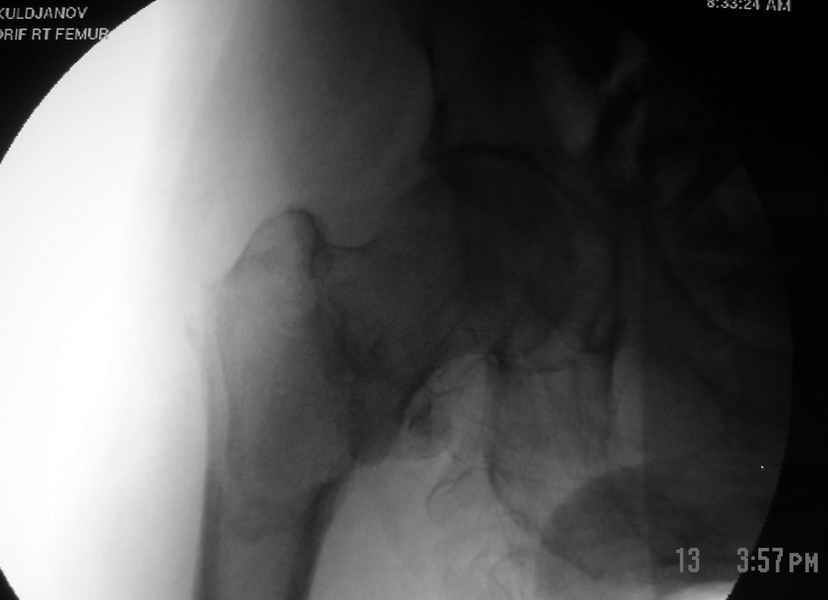

Второй случай тоже репозиция из малого доступа, больному 19 лет, множественные огнестрельные повреждениия конечностей, живота и черепа, правая конечность холодная, без пульсации. Ортопедический диагноз: огнестрельный перелом правого бедра. При срочной ангиографии повреждения сосудов не подтвердилось, конечность из-за ургентности состояния больного зафиксирована временным наружным фиксатором и больной оставлен на операционном столе для срочной лапаротомии хирургической службой.

Больной долго оставался нестабильным, только на 14 день удалось заменить на антеградный интромедуллярный штифт TFN (trochanteric femoral nail) SmithNephew. После неудачной попытки закрытой репозиции, несмотря на использование "joystick", проксимальный стержень от

наружного фиксатора, (перелом начал срастаться) репозицию провели из малого доступа, затем остальные этапы операции.

Случай был представлен из-за того, что больного оперировали после наружной фиксации и был риск инфекцирования через места проведения стержней (на снимках), прошло больше 3 месяцев, выписан из амбулаторной службы из-за отсутсвия надобности дальнейшего наблюдения.